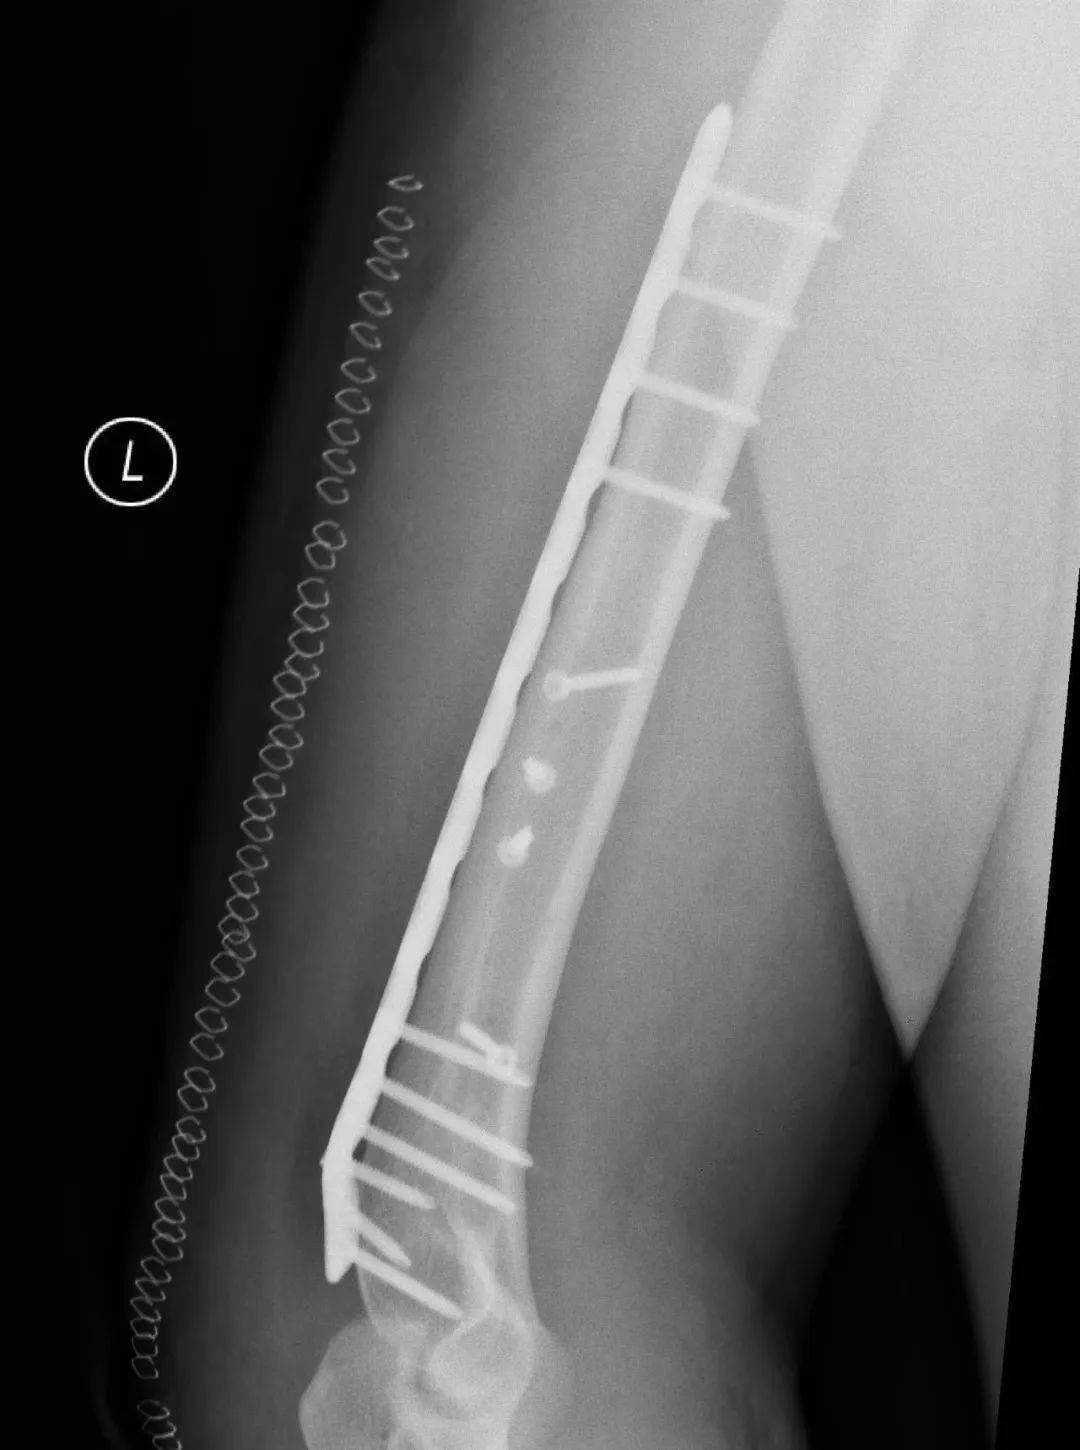

肱骨干骨折的治疗方法包括非手术治疗、闭合复位髓内钉内固定术和切开复位钢板螺钉内固定术等多种方式。采用非手术治疗时,可对患肢进行悬垂石膏固定或行闭合复位后使用上臂U型石膏固定,2-3周后解放肘关节,使用功能支具固定10-12周。由于扳手腕导致的肱骨干骨折几乎均为肱骨远端三分之一螺旋形骨折,闭合复位髓内钉内固定术不适合这类骨折,切开复位钢板螺钉内固定术是这类骨折的最佳的手术治疗方式。

图 切开复位钢板螺钉内固定术